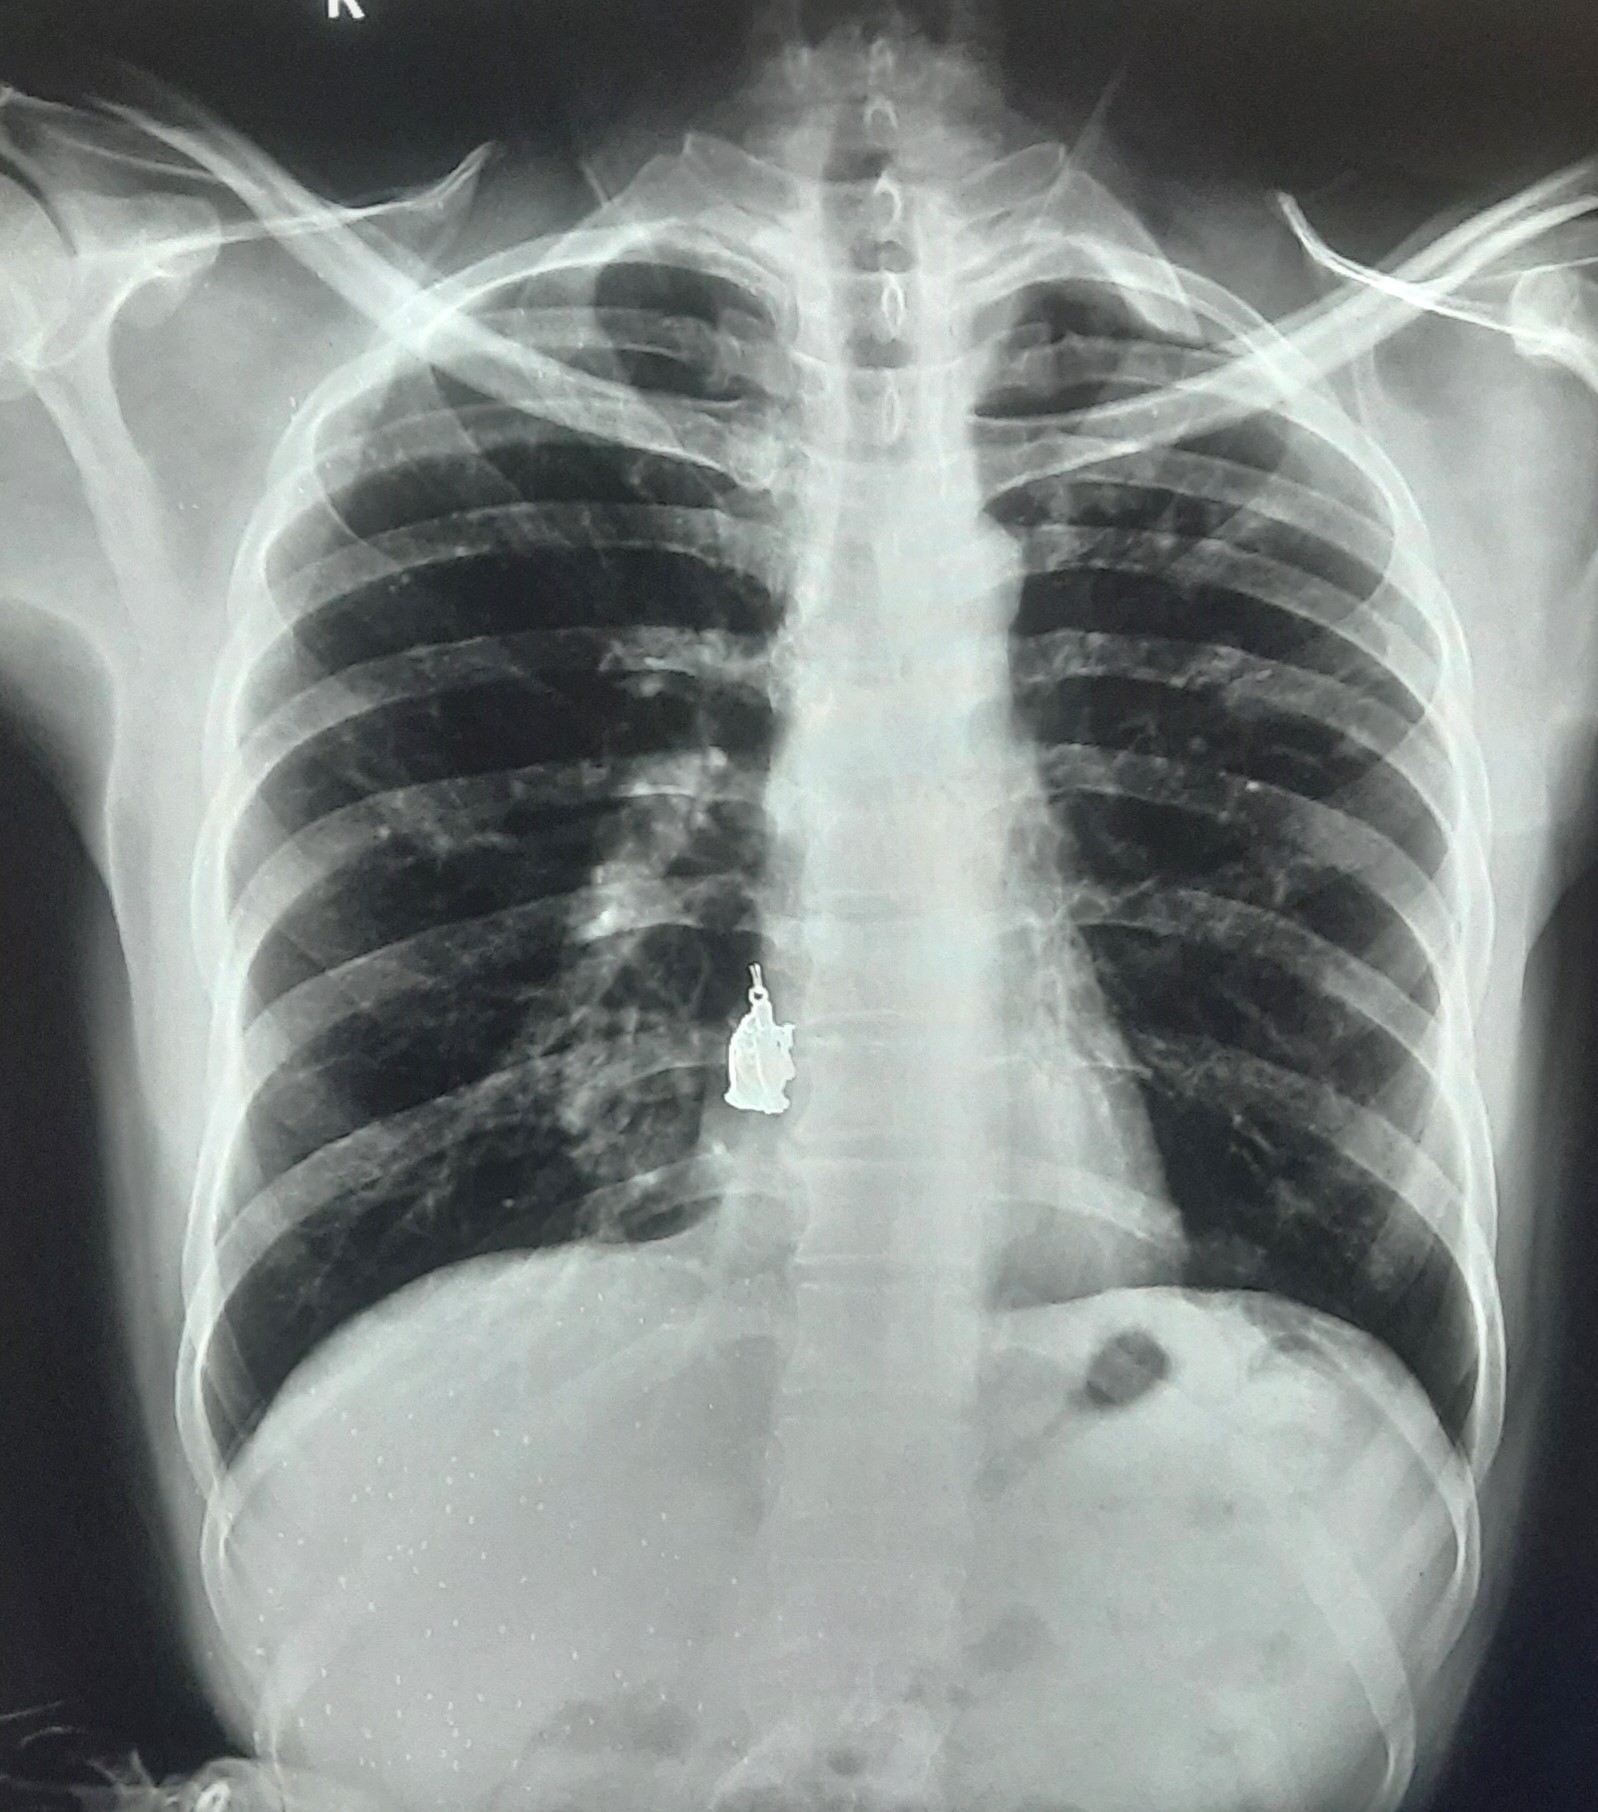

| 205 | IGGMC, Nagpur, Nagpur | P2 | 29-4267 | MOHAMMAD HANIF SUREYYA | Consent taken on Paper | 55 Yrs. |

Provisional Diag : PTB?

Final Diag : PNAEMOTHORAX /CLINICALLY DIAGNOSED PTB |

TB Case (Confirmed) | LEFT SIDED PNAEMOTHORAX | Abnormality visible on x-ray |